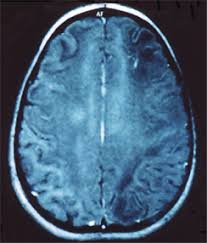

D-2- aciduria hidroxiglutárica (D-2-HGA) es caracterizado por retraso del desarrollo, convulsiones, tono muscular débil (hipotonía), y anormalidades en el cerebro, que controla muchas funciones importantes, tales como el movimiento muscular, el habla, la visión, el pensamiento, las emociones y la memoria.

L-2- aciduria hidroxiglutárica (L-2-HGA) afecta particularmente a una región del cerebro llamada el cerebelo, que está implicado en la coordinación de movimientos. Como resultado, muchos individuos afectados tienen problemas con el equilibrio y la coordinación muscular (ataxia). Las características adicionales de la L-2-HGA pueden incluir retraso en el desarrollo, convulsiones, dificultades en el habla, y una cabeza inusualmente grande (macrocefalia). Por lo general, los signos y síntomas de este trastorno comienzan durante la infancia o la niñez temprana. El trastorno empeora con el tiempo y por lo general resulta en la discapacidad grave en la edad adulta temprana.

El tipo combinado D, L-2- aciduria hidroxiglutárica (D, L-2-HGA) provoca graves alteraciones cerebrales que se manifiestan en la infancia temprana. Los niños afectados tienen convulsiones severas, tono muscular débil (hipotonía), y problemas respiratorios y de alimentación. Por lo general, sólo sobreviven en la infancia o la niñez temprana.